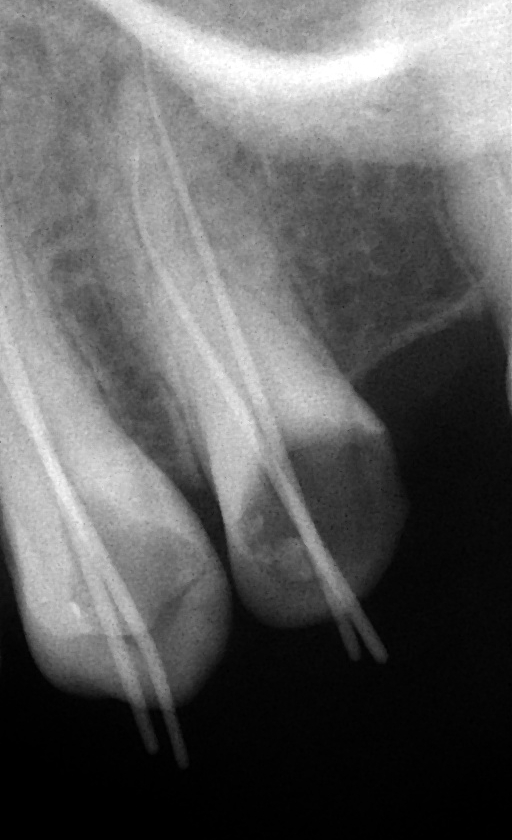

Kontrolní měřící rentgen